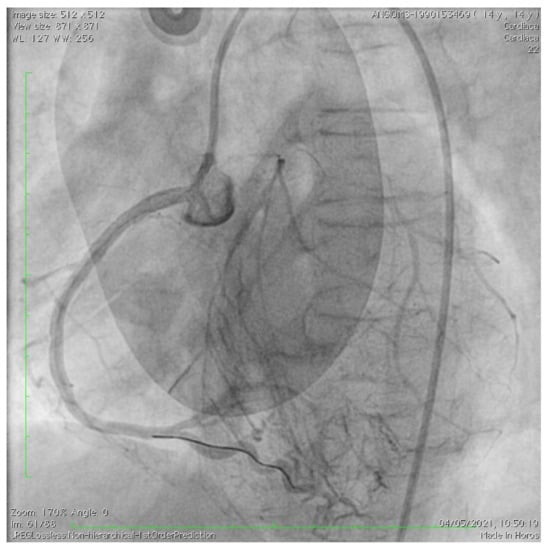

Acute Coronary Syndrome Treated with Percutaneous Coronary Intervention in Hutchinson–Gilford Progeria

De Simone, L.; Chiellino, S.; Spaziani, G.; Porcedda, G.; Calabri, G.B.; Berti, S.; Favilli, S.; Stefani, L.; Santoro, G. Acute Coronary Syndrome Treated with Percutaneous Coronary Intervention in Hutchinson–Gilford Progeria. Children 2023, 10, 526. https://doi.org/10.3390/children10030526